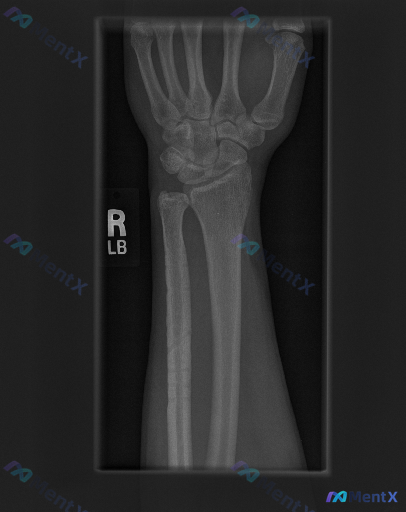

整理到一份右手腕影像学资料及深度评估思路,分享给大家一起讨论。 基本影像表现(右手腕正位X光片) - 骨骼完整性:右侧尺骨茎突处可见明确骨皮质中断,断端有分离移位;桡骨远端关节面、腕骨、掌骨基底未见明确骨折线或骨质破坏。 - 关节与对位:桡腕关节、腕骨间关节间隙清晰,排列大致规则;尺骨茎突骨折处伴随...